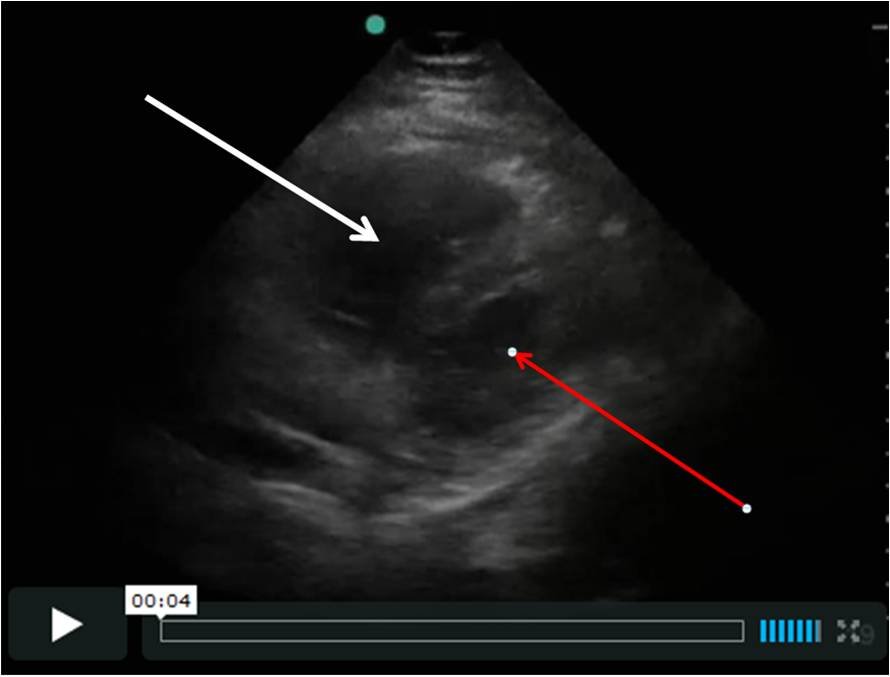

| The thick white arrow shows the right ventricle, which is dilated. The thin red arrow shows the left ventricle, which should not be smaller than the RV, as it is here. |

This self-trained EMT rolled the ultrasound into the patient’s

room and found this very large RV. The patient underwent immediate

CTPA, had a submassive saddle embolus, and underwent immediate catheter directed

thrombolysis.